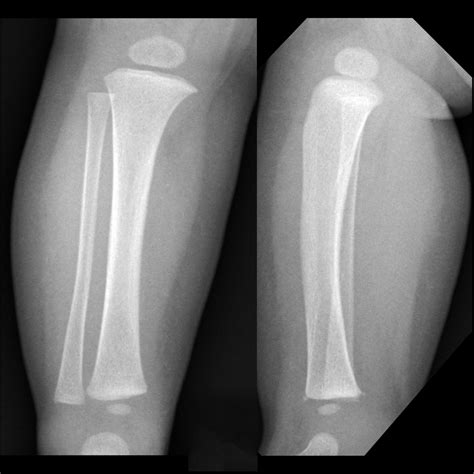

A Bucket Handle Fracture is a specific type of fracture where a segment of bone is displaced, often in a manner that resembles the handle of a bucket. This type of fracture is commonly seen in the knee, particularly in the medial meniscus, but can also occur in other joints. The fracture typically involves a longitudinal split in the bone, with the displaced segment often remaining attached to the surrounding ligaments or tendons.

• Imaging Tests: X-rays, MRI, or CT scans to visualize the fracture and determine the extent of the damage.

Imaging tests are crucial for confirming the diagnosis and planning the appropriate treatment. X-rays can show the fracture line, while MRI and CT scans provide detailed images of the soft tissues and bone structure.